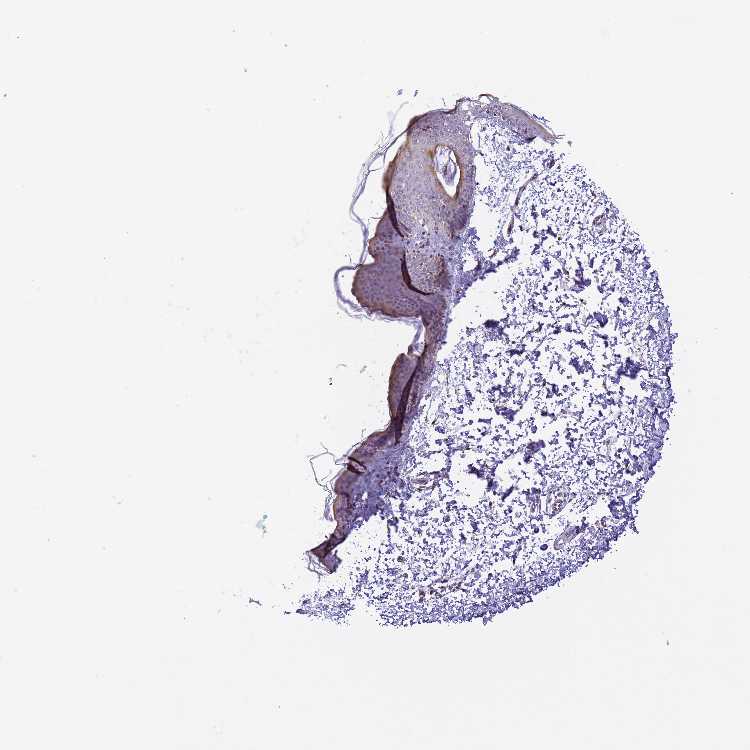

SKIN 1 - Antibody stainingi

Antibody staining in the annotated cell types in the current human tissue is reported as not detected, low, medium, or high, based on conventional immunohistochemistry profiling in selected tissues. This score is based on the combination of the staining intensity and fraction of stained cells.

Each image is clickable and will lead to virtual microscopy that enables deeper exploration of all samples and also displays staining intensity scores, fraction scores and subcellular localization as well as patient and tissue information for each sample.

Antibody HPA043979

Langerhans Not detected

Fibroblasts Low

Keratinocytes Low

Melanocytes Not detected